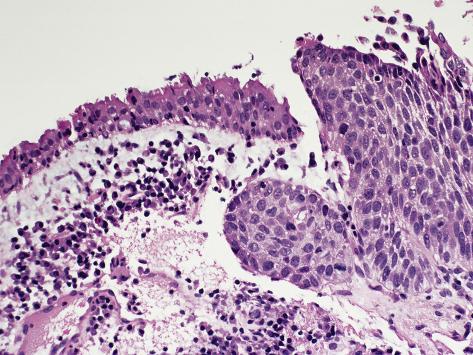

Malignant Epithelial Neoplasms Bland neuroendocrine neoplasm. Rare mitotic figures. Focal necrosis. Prominent nucleoli Non-specific. NEOPLASMS OF LUNG, PLEURA, AND MEDIASTINUM Author: UNC-SOM Last modified by: School of Medicine Created Date: ... Fetch Document